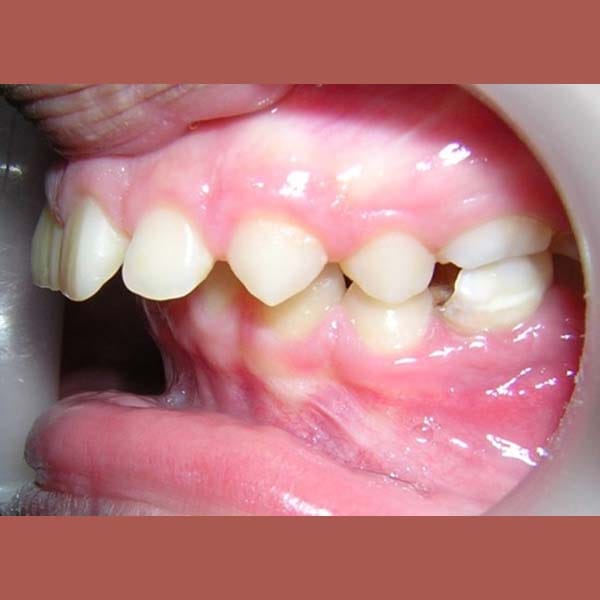

BEFORE

A case of severe protrusion in the upper anterior teeth that we treated with Mandibular Anterior Repositioning Appliance at first stage -which is is used to move the lower jaw forward- and then completed the treatment using a conventional orthodontic device.